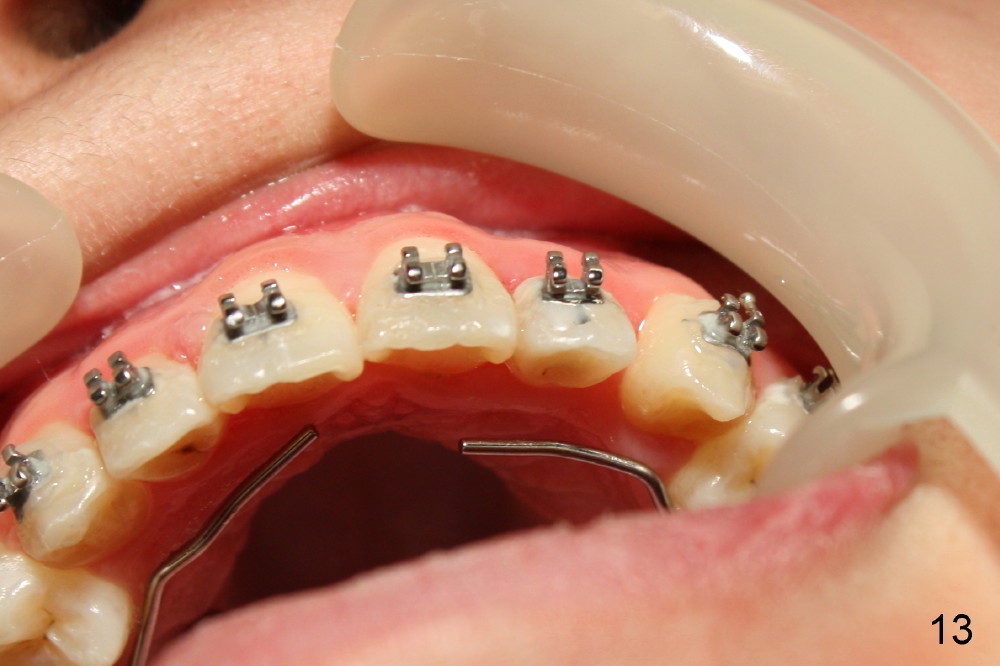

Another one month later, UL2 is moved labially and a bracket is placed (upside down in order to fix torque problem associated with cross bite correction). Surprisingly, it works perfectly: UL2 orientation is right (Fig.12,13,14). The distal diastema (Fig.14 <) is to be closed by power chain. The palatal expander is removed since the posterior cross bite has been a little overcorrected (Fig.14,15, as compared to Fig.1,2,4-7).